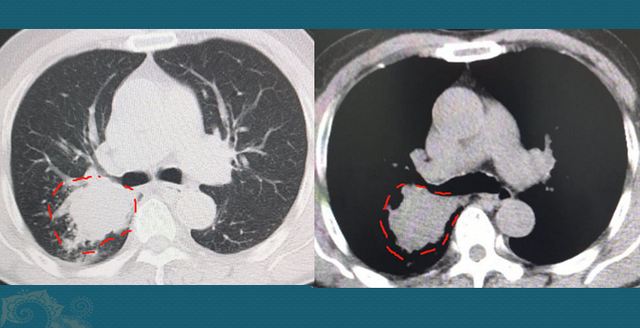

我们先不争论这些,看看这个病人的CT片:

右侧肺门区一个不规则肿块,最大径线4.6cm,远侧肺组织里有一些小点片状炎症,这是由于肿瘤堵塞气道,引起的壅闭 性肺炎。

从生长速率 上看,肺鳞癌通常比腺癌更快,破损 力更大(某些低分化腺癌也很快)。我们搜索这位病人既往的检查资料,发现他2年前由于 伤风、咳嗽、发烧做过一次胸部CT,其时的支气管和肺脏是完全正常的: